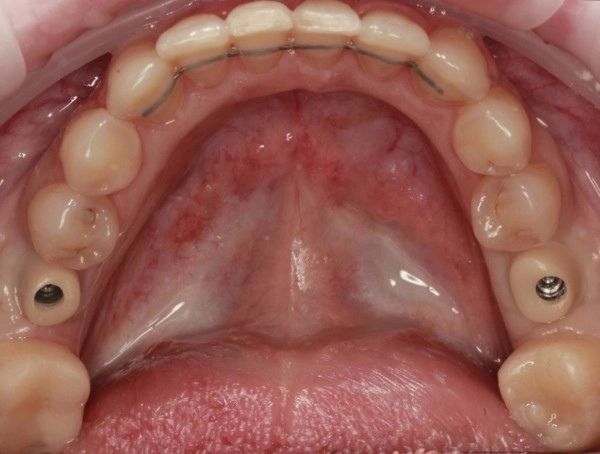

Установлены 2 коронки на импланты с индивидуальным циркониевым абатментом. На задние сильно разрушенные жевательные зубы установлены керамические накладки.

Работа врача - ортодонта Глуховой Татьяны Александровны и врача - ортопеда Никитина Никиты Юрьевича.